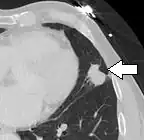

- Margin morphology: a spiculated margin is a risk factor for cancer.[8] Benign causes tend to have a well defined border, whereas lobulated lesions or those with an irregular margin extending into the neighbouring tissue tend to be malignant.[10] In particular, spiculations are highly predictive of malignancy with a positive predictive value up to 90%.[9] Also, a "notch sign", which is an abrupt indentation of the nodule, increases the risk of cancer, but may also be found in granulomatous diseases.[9]

-

subpleural nodule.[9] -

Round well-delineated solid lung nodule with smooth border.[9] -

Lobulated nodule.[9] -

Spiculated lung nodule.[9] -

A "notch sign".[9] -

A triangular perifissural node can be diagnosed as a benign lymph node.[9]